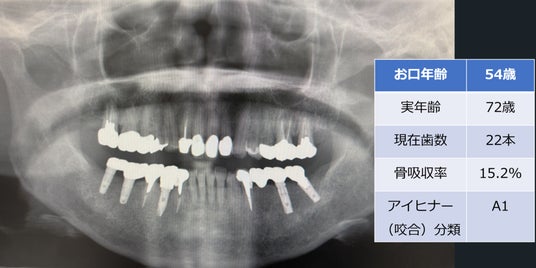

「お口年齢AI」は、歯科パノラマエックス線画像から、現在歯数、インプラント数、アイヒナーの咬合分類、歯槽骨吸収量などの抽出したデータと、生年月日・性別の情報から、「お口年齢」を算出するシステムとなっています。

本システムでは、生活習慣病である歯周病に関連する歯槽骨吸収量も加味して判定しており、また抜歯後にブリッジやインプラント治療を行った場合などは、顕著に「お口年齢」が若年指標として算出されます。

この「お口年齢AI」システムでは、奥歯などでの咬み合わせ状態も確認できるため、お口のトラブルをスクリーニングすることができます。